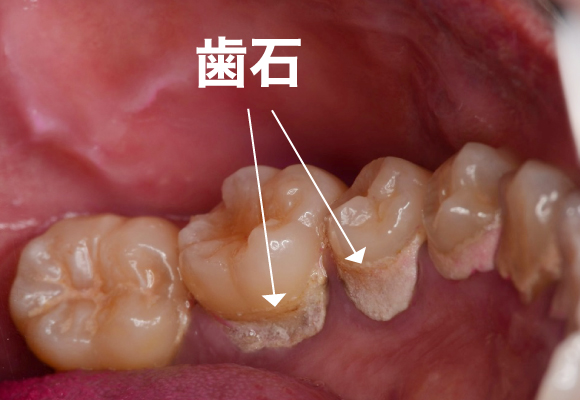

■プラークが固まって歯に頑丈にこびりついたものを歯石といいます。

歯磨きをしやすいように大まかな歯石を取る

歯茎と歯の境目に隠れた歯石を細かく取る